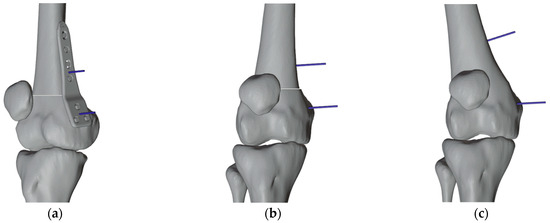

2.4. Design and Production of the Patient-Specific Instrumentation

2.4.1. PSIs Design for the Right Femur

2.4.2. PSI Design for the Left Femur

2.4.3. 3D Printing of PSI and Sterilization